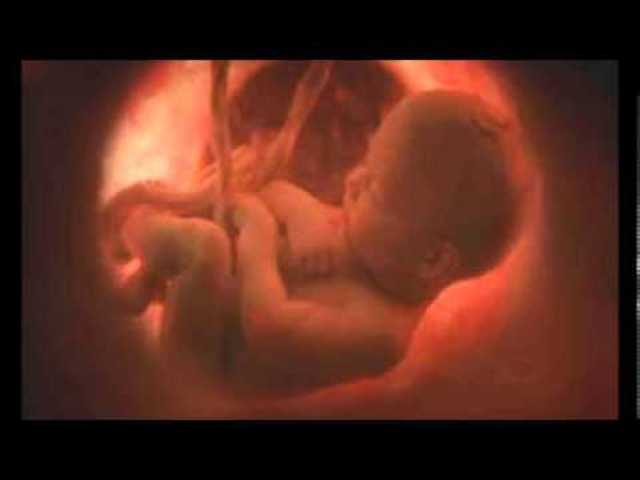

• Period: to

Etapa fetal

El embrión es llamado feto y a medida que crece el feto dentro del útero materno, realizar las funciones que le permitirá al recién nacido vivir en forma independiente.